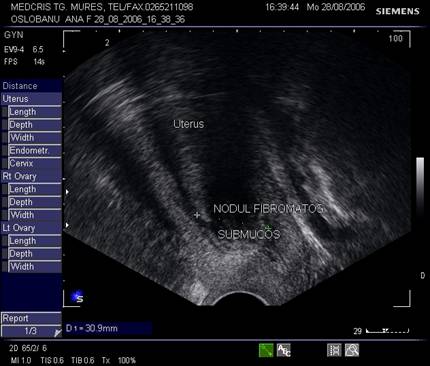

Aproximativ 90% din fibroame (leiomioame) apar la nivelul corpului uterin. Se descriu, faza miomatozei difuze, fibroame intramurale, subseroase, submucoase, intraligamentare.Mioamele prezinta margini bine delimitate fata de miometru la ecografie, continand arii de mai mare sau mai mica ecogenitate in functie de modificarile degenerative.[1,6]

Fig. nr.385. Nodul submucos ce deformeaza cavitatea uterina, ecografie transvaginala